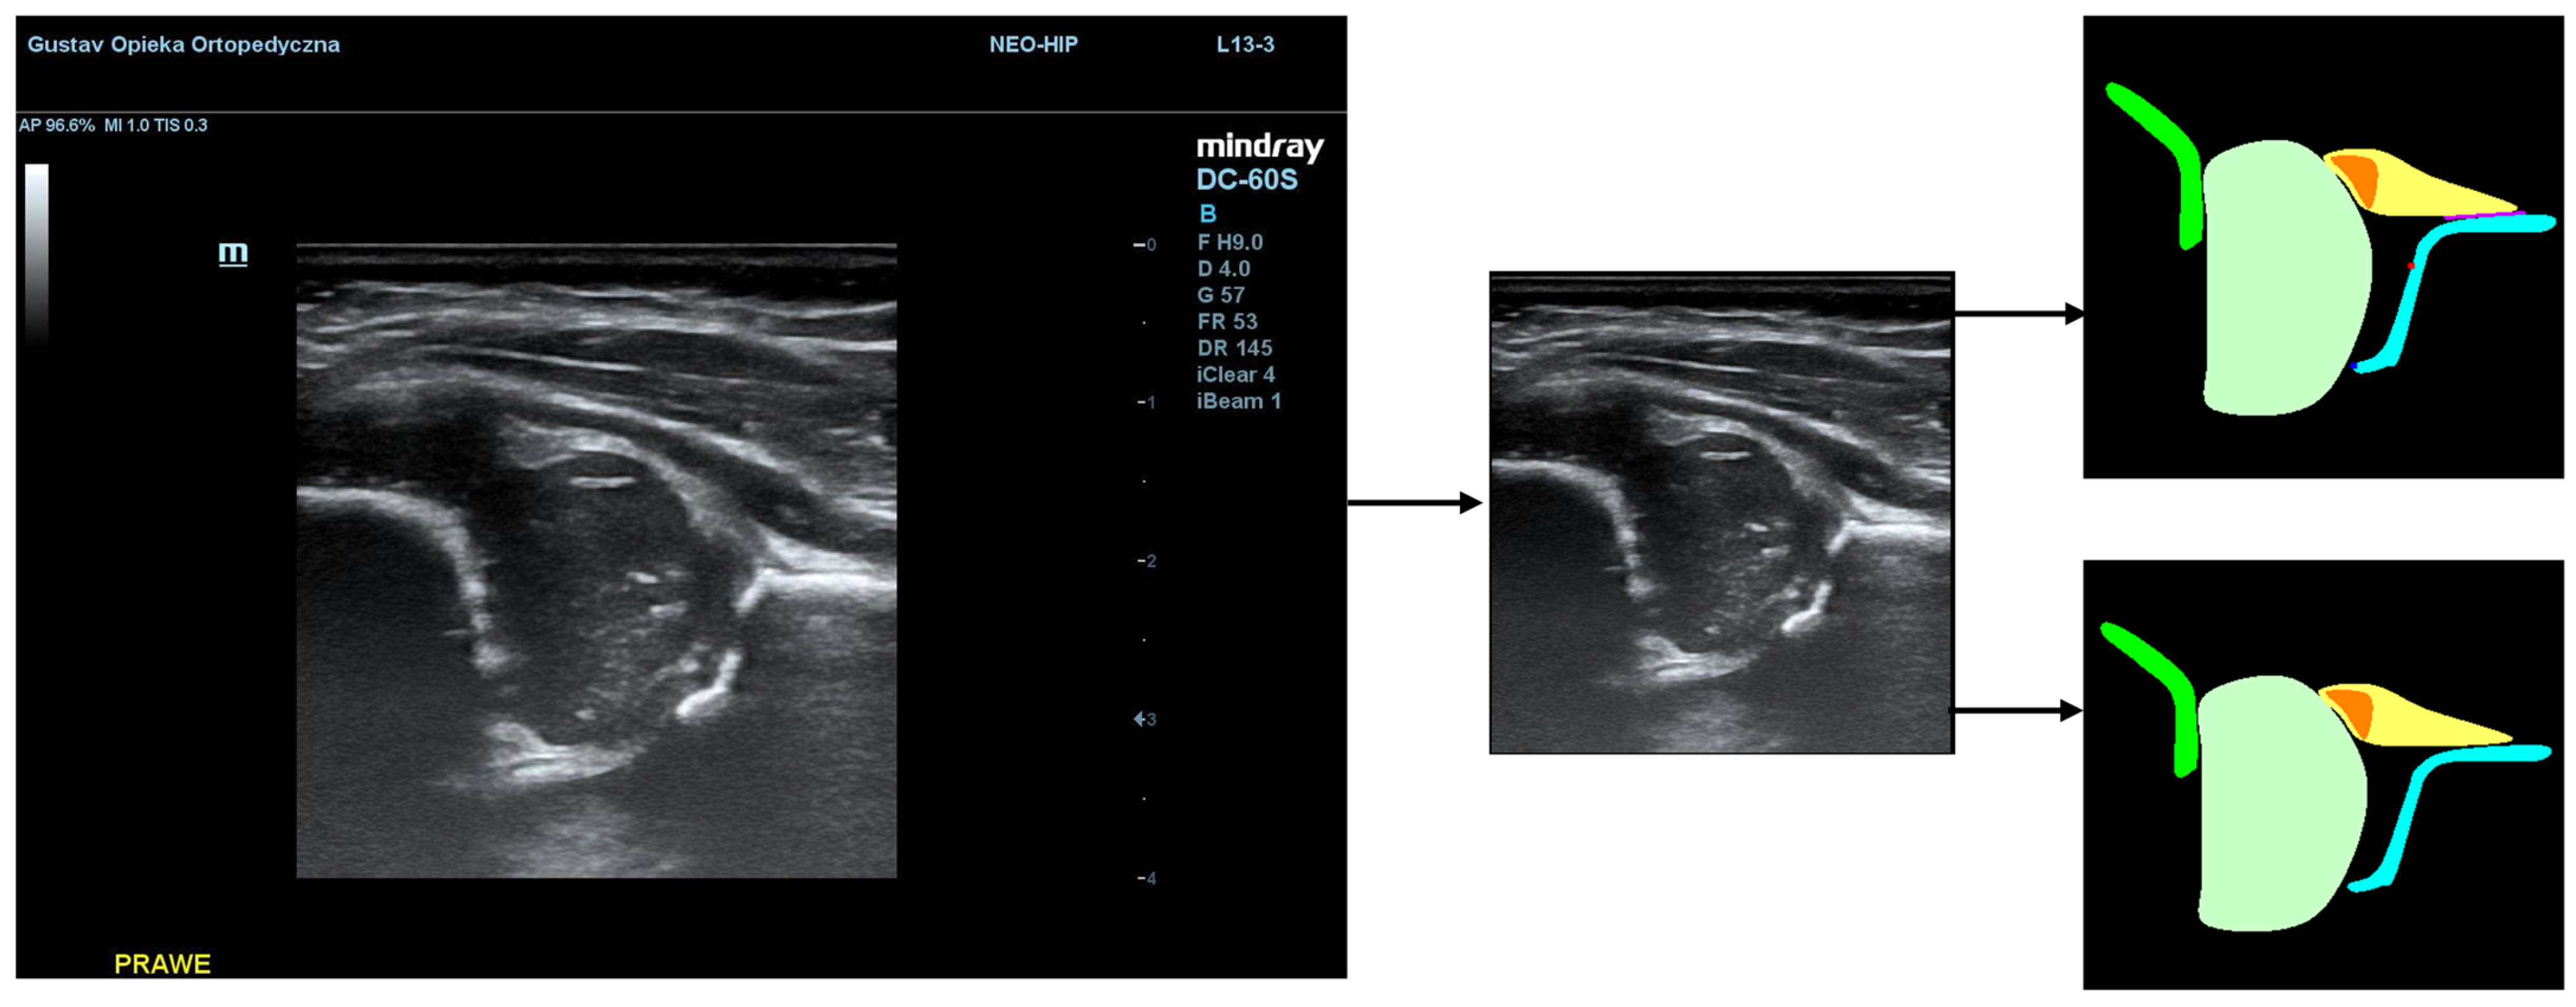

To illustrate the performance of the segmentation model, a comparison is presented between the labels obtained by the segmentation model and the ground truth labels. Two models were analyzed: Model-8 (generating segments for eight classes) and Model-5 (generating segments for five classes). Both the cases with the highest quality model labels and the cases where the model labels were less accurate are presented. Figure 3 shows one of the best cases, in which Model-5 and Model-8 accurately labeled the classes relative to the doctor’s labels. The worst-case scenario was also analyzed, in which the prediction results differ significantly from the ground truth labels (Figure 4).

Figure 4. Low-quality model labels (upper—Model-8) and (lower—Model-5). Annotated mask on the left, model mask on the right.

Jcm 14 06332 g004